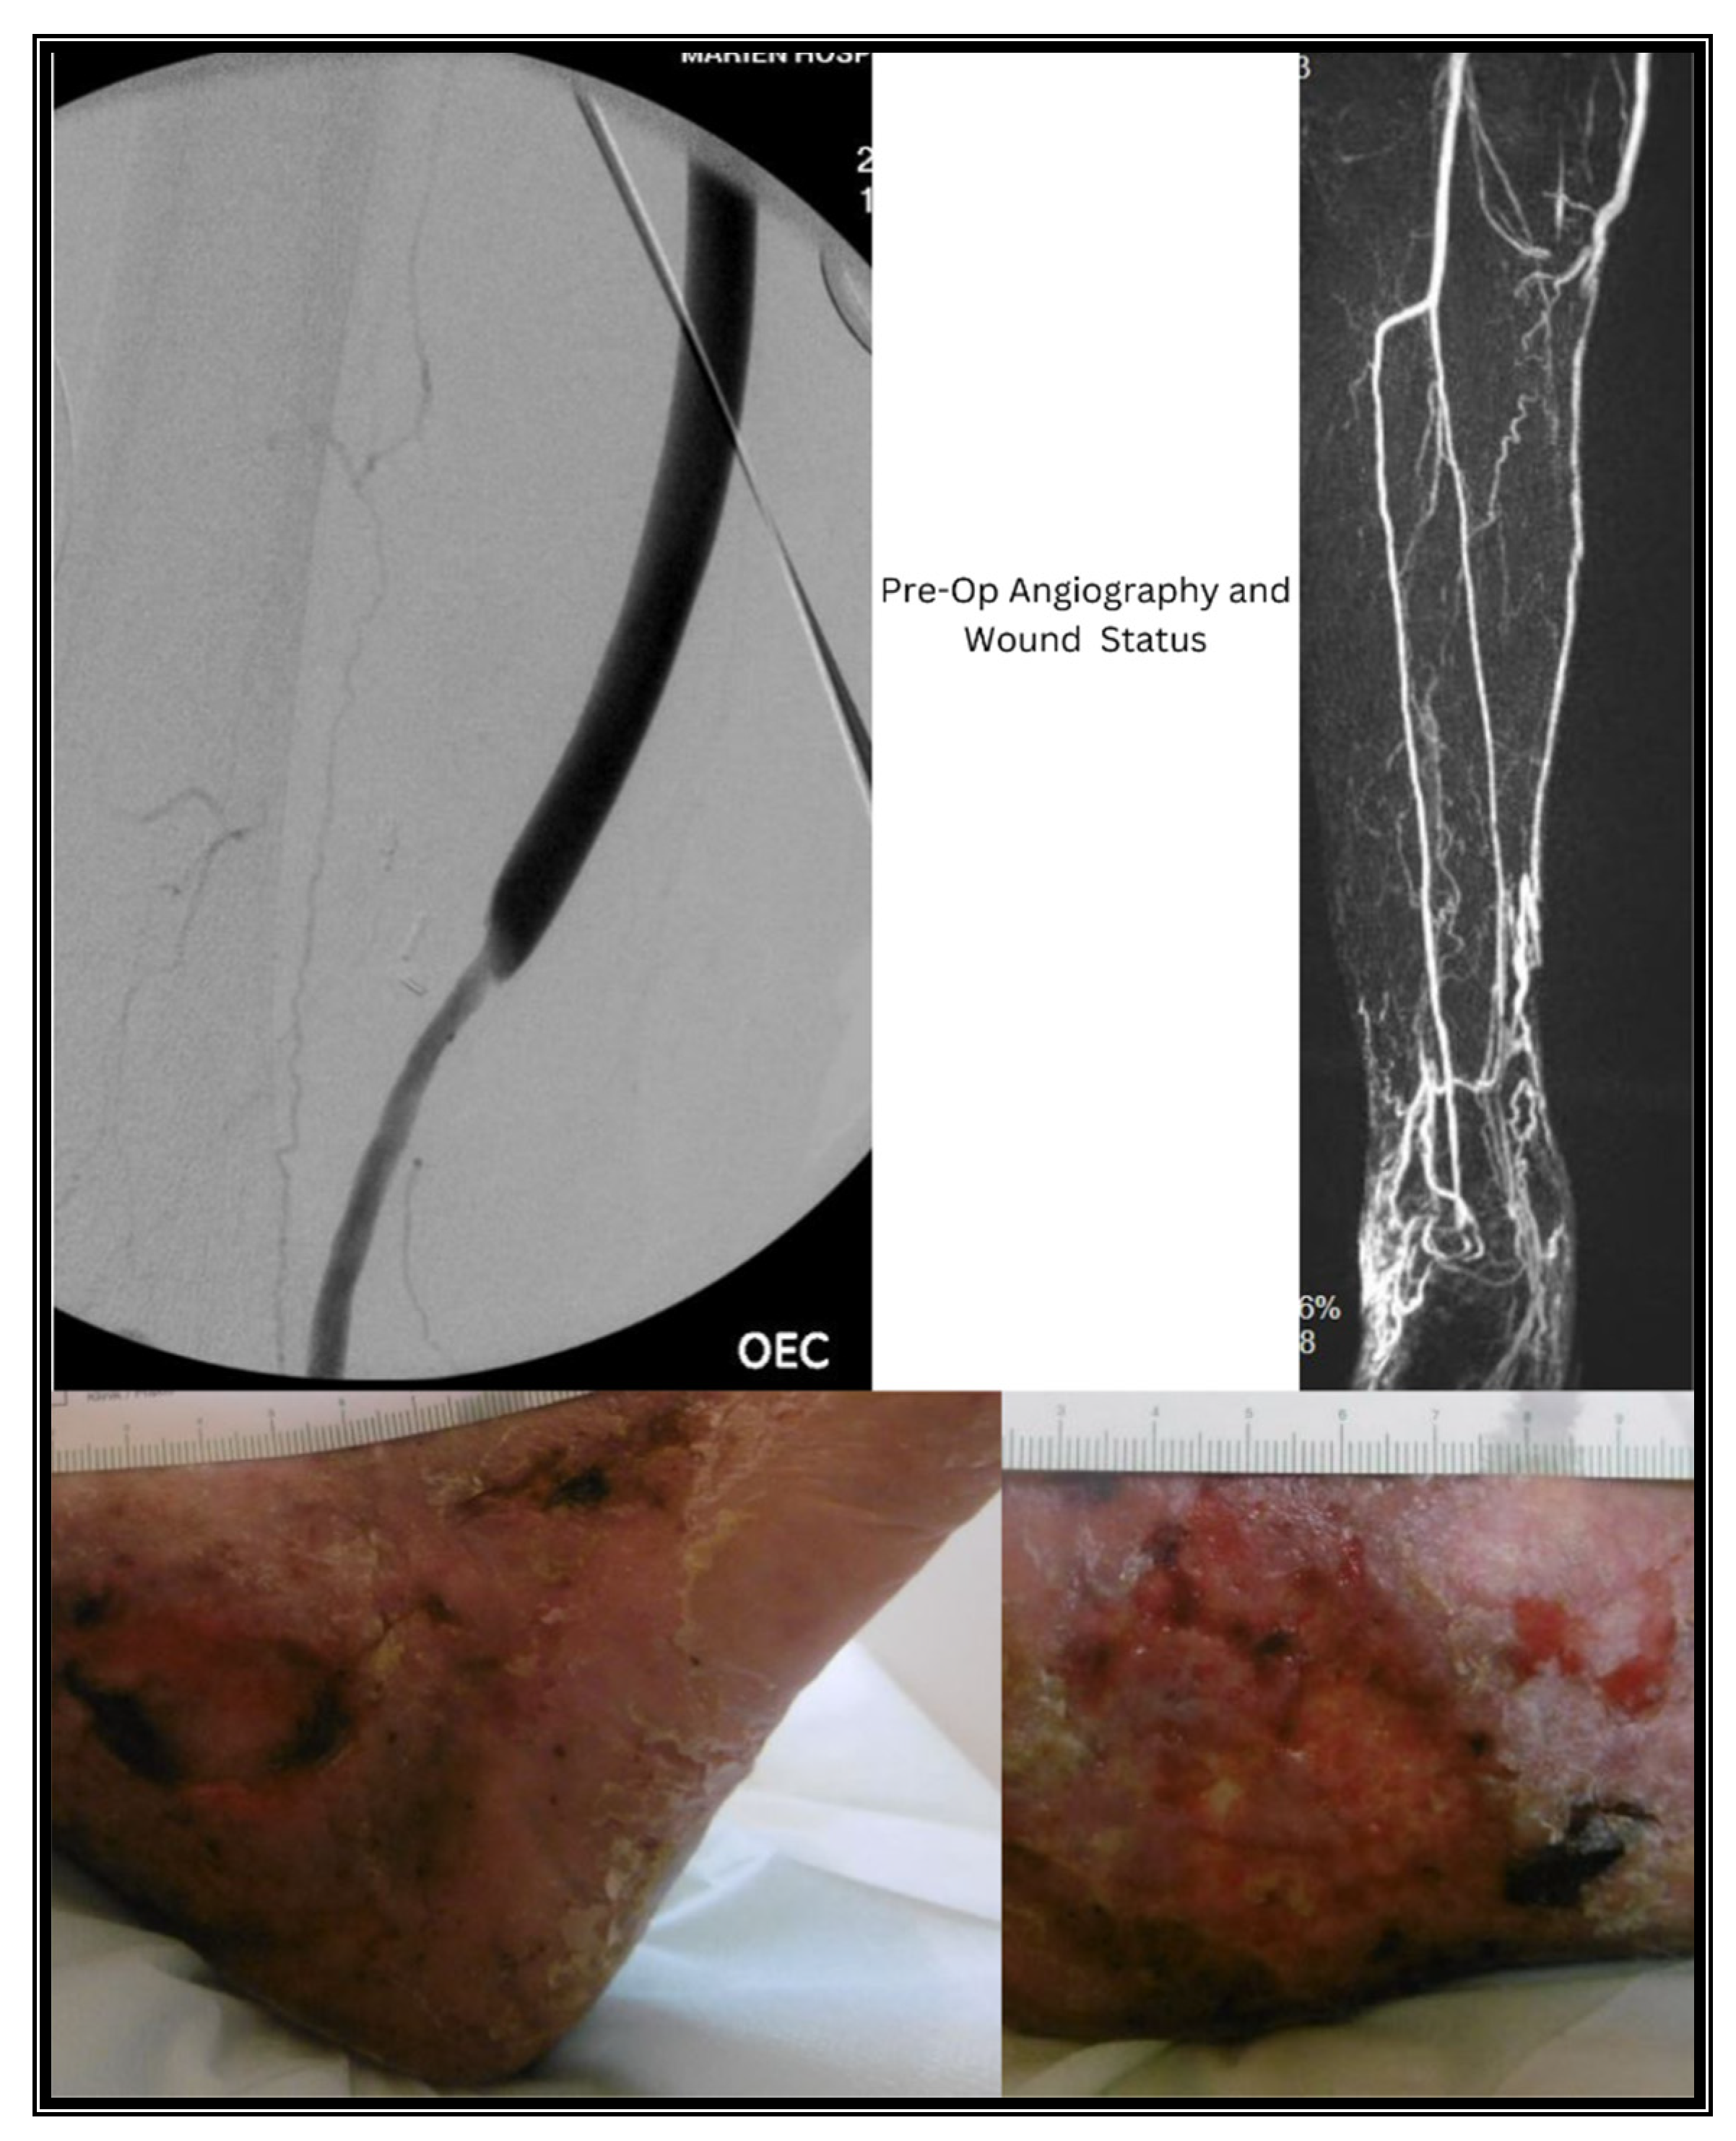

2. Case Presentations

2.2. Case II

3.2. Case II